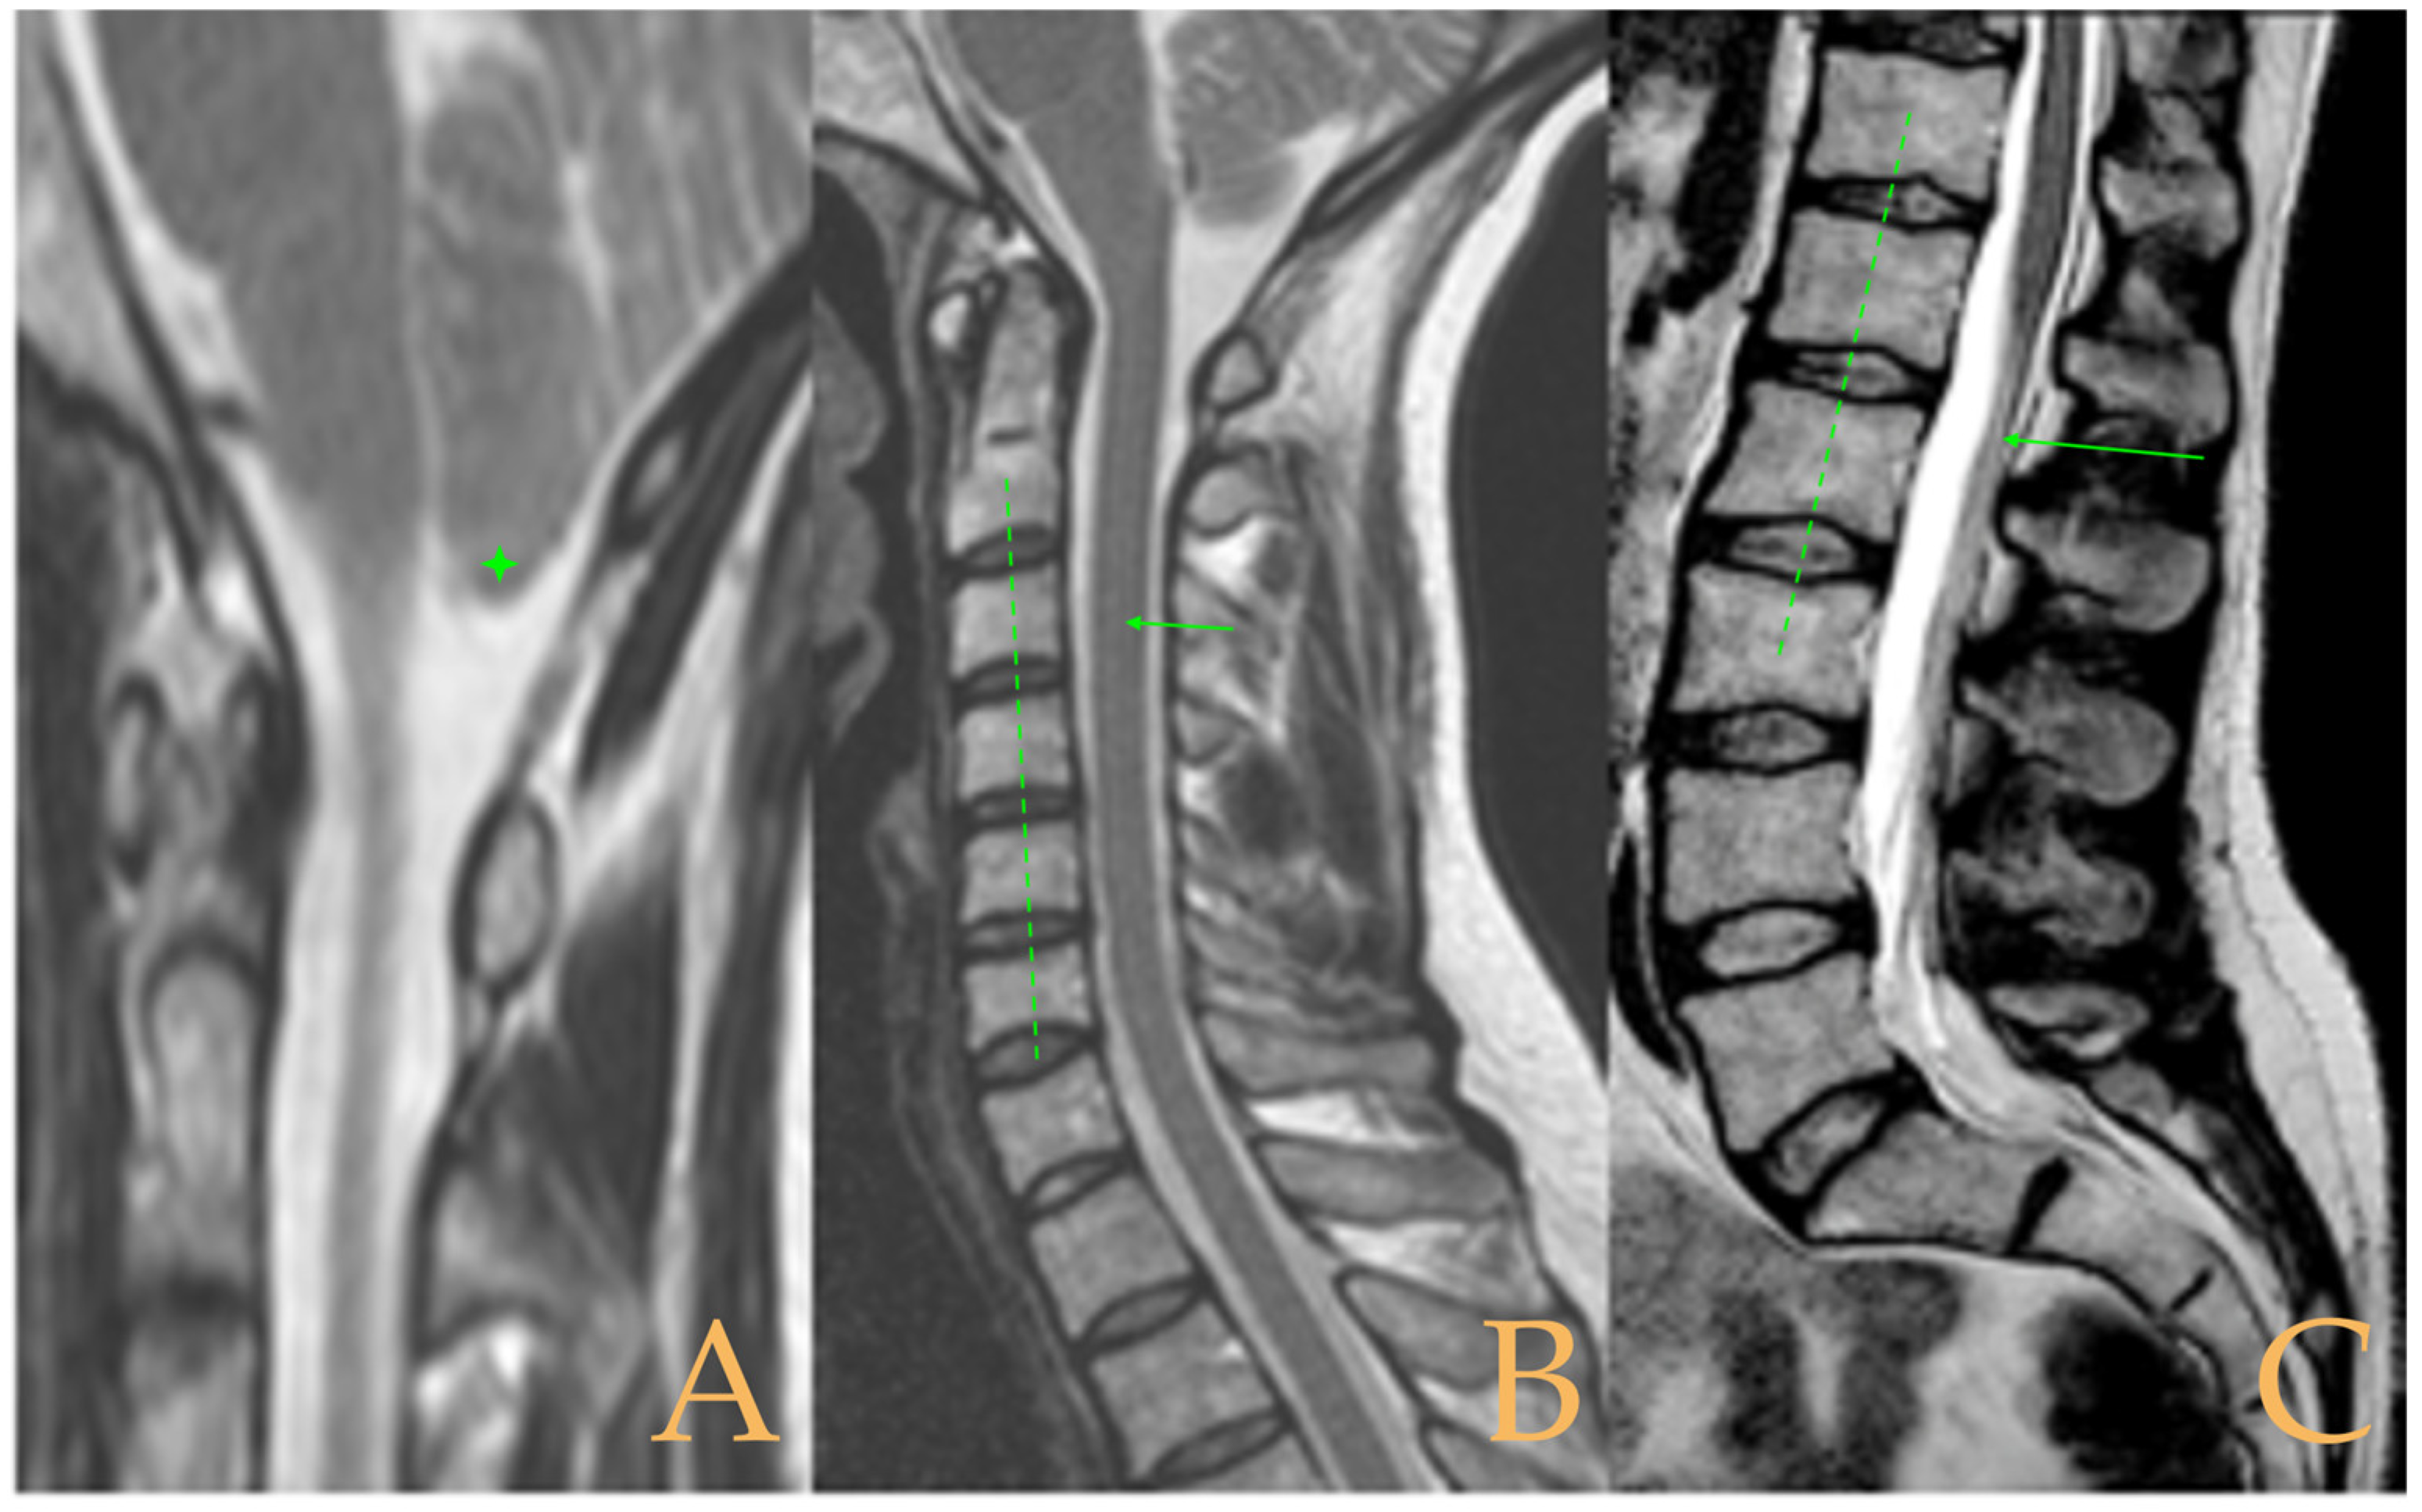

The cranio-vertebral magnetic resonance showed empty sella turcica, discrete descent of the cerebellar tonsils, C4-C5-C6 disc protrusions and cervical hypermobility with a tense medullary aspect in flexion in the incorporated dynamic test, and conus medullaris at the height of the TH12-L1 disc (Figure 3). No scoliosis was observed in the full-spine X-rays. The patient was not operated on. Cases 8 and 9 were very similar and involved previously diagnosed cranio-cervical and atlantoaxial instability. The patient used a cervical collar, as she was afraid that she might suffer spontaneous cervical luxation.

Figure 3.

Imaging of patient 3. A: Empty sella turcica (arrow); B: discrete descent of the cerebellar tonsils (arrow); C: C4C5 and C5C6 disc protrusions (arrows); and D: tense spinal cord in cervical flexion (interrupted line).

The MRI showed descent of the cerebellar tonsils, increased supracerebral space, and postsurgical repercussions of the sphenoid sinus in the right half. Empty sella turcica. Micro lacunae bilaterally in hemispheres, basal ganglia, and white matter. Straightening of the cervical spine. Cervical spinal cord with tense aspect and inferior lateral displacement, the thoracic portion appears tense with slight ischemia and oedema. Protrusions: C3-C4, C5-C6-C7, T7-T8, and L3-S1. Lumbar hyperlordosis. Sacrococcygeal hyperkyphosis. Ischemia and oedema in epiconus. Low conus medullaris at the level of the upper third of L2 vertebral body. Tarlov cyst at S2 (left) (Figure 4). Proximal filum terminale externum visible. Levoconvex lumbar scoliosis on the spine X-ray estimated at 6°; dextroconvex cervical and thoracic scoliosis estimated at 4°.

Figure 4.

Imaging of patient 4. A: Cranial MRI with visible descent of the cerebellar tonsils in the foramen magnum (stars); B: cervical MRI with straightening of the cervical spine (interrupted line) and cervical multiple disc disease (arrows); and C: lumbar MRI with conus medullaris at the upper third of L2 (arrow).

Magnetic resonance imaging showed moderate descent of the cerebellar tonsils, mild multiple disc disease, and low-lying conus medullaris at the level of the upper third of the L2 vertebra (Figure 5). The full-spine X-ray ruled out scoliosis.

Figure 5.

Imaging of patient 5. A: Moderate descent of the cerebellar tonsils (star) and B: conus medullaris in upper third of L2 (arrow).